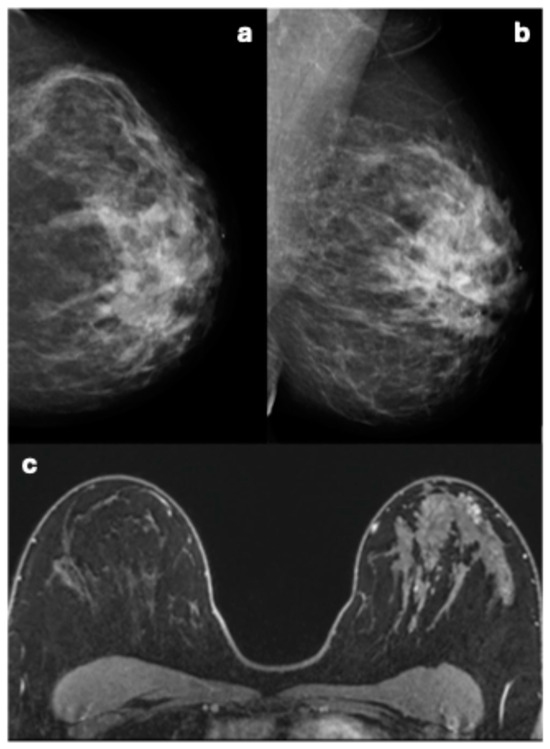

3.3. Mammographic Imaging Features and Corresponding Pathology Outcome of Breast Cancers